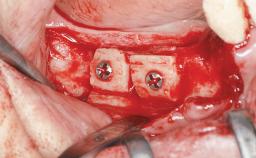

Bone Augmentation Horizontal|Sinus Floor Elevation|Staged|Vertical

Augmentation Materials Autogenous chips|Autogenous block(s)

Bone Volume Deficient vertically or deficient vertically AND horizontally